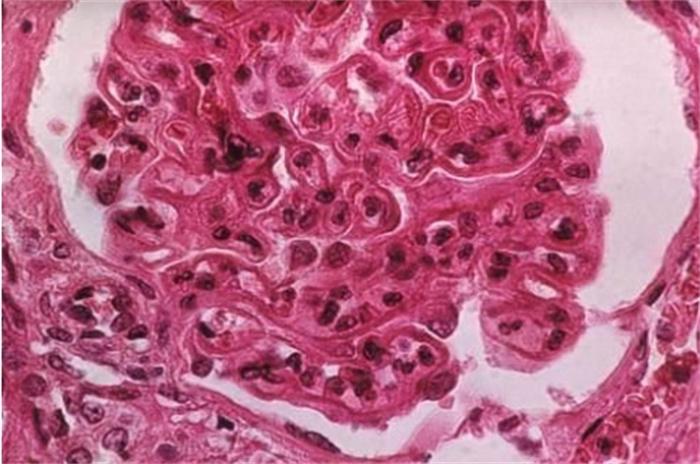

红斑狼疮属于一种免疫系统疾病,会导致心血管、肾脏、消化系统、肺、血管、眼部、血液系统等多个器官损伤。红斑狼疮最为明显的症状就是在面颊出现蝴蝶形的红斑。红斑狼疮的症状复杂多样,有的可能表现为心功能受损,有的可能表现为关节痛,还有一些人的症状是反复出现口腔溃疡,而有些人则会出现肾脏受累的临床表征,比如血尿或蛋白尿,还有可能会伴随着肾功能不全。很多人会认为是皮肤过敏,到皮肤科看,也有些人会去骨科或者是肾内科去看,但是都找不到病因。实际上红斑狼疮需要看的是风湿免疫科。